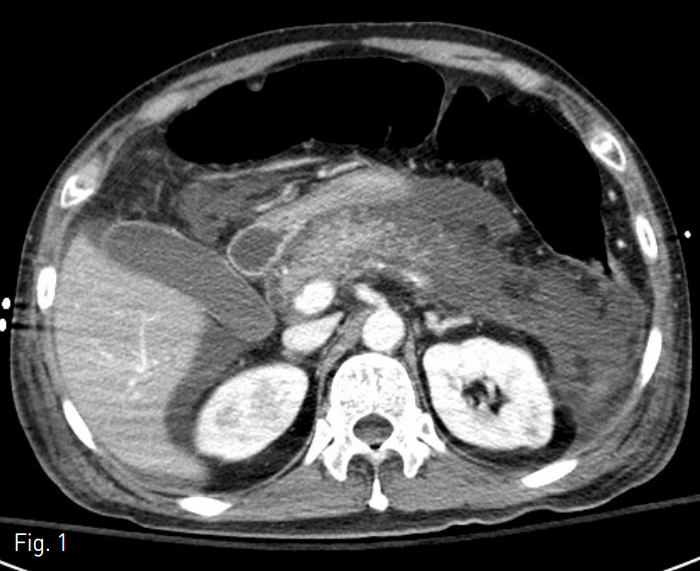

응급실 내원 후 시행한 전산화 단층촬영에서 비교적 정상실질의 고음영이 유지되어 있는 췌장 두부와는 달리 췌장 경부, 체부에는 경계가 정확히 그려지지 않는 저음영 구역이 보이고 있으며 조영 증강의 정도도 떨어지는 것이 보임. 이와 더불어 췌장주위구역과 전방콩팥 주위공간에 구획화된 액체 저류가 있고 오른 결장주위 공간으로도 액체 저류가 보이고 있음. 해당 액체 저류들이 경계가 매우 잘 그려지는 격막에 둘리싸여 있지는 않았으나 주변 복막이 상대적으로 두꺼워 보이면서 미약한 조영 증강도 보이고 있어 감염된 액체 저류의 가능성이 있을 것으로 생각되었음. 이와 더불어 장이 전체적으로 공기에 의해 늘어나 있는데 장마비가 동반되어 있는 것으로 보임. 이와 같은 소견은 급성 괴사성 췌장염과 이에 동반된 췌장 주위 액체 저류의 소견임 (Fig. 1). 전산화 단층촬영에서 방사선비투과성 담석은 보이지 않았으며 췌장 동맥의 거짓동맥류도 없었음.

Fig. 1

Contrast-enhanced axial CT scan shows diffuse pancreas parenchymal swelling, decreased enhancement of pancreas body and tail portion, and peripancreatic acute necrotic collection, other fluid collection at right anterior pararenal space. In conclusion, these findings are compatible with acute necrotizing pancreatitis with associated acute necrotic and peripancreatic fluid collection.